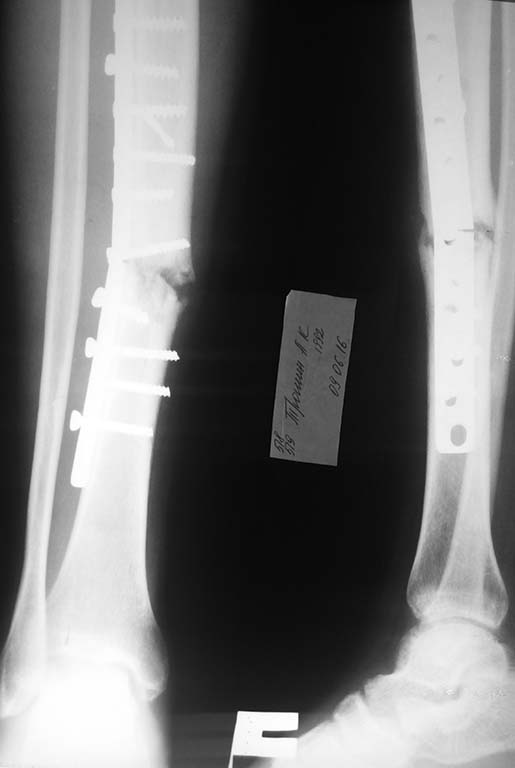

В данном случае если просто поменять накостную пластинку, не трогая

концы отломков, не повлияет ли это на костное сращение??? Больной

оперирован в Феврале 2016г. Не соблюдая рекомендации, ходил без

костылей. В начале Июня сломал пластинку. Ваше мнение?